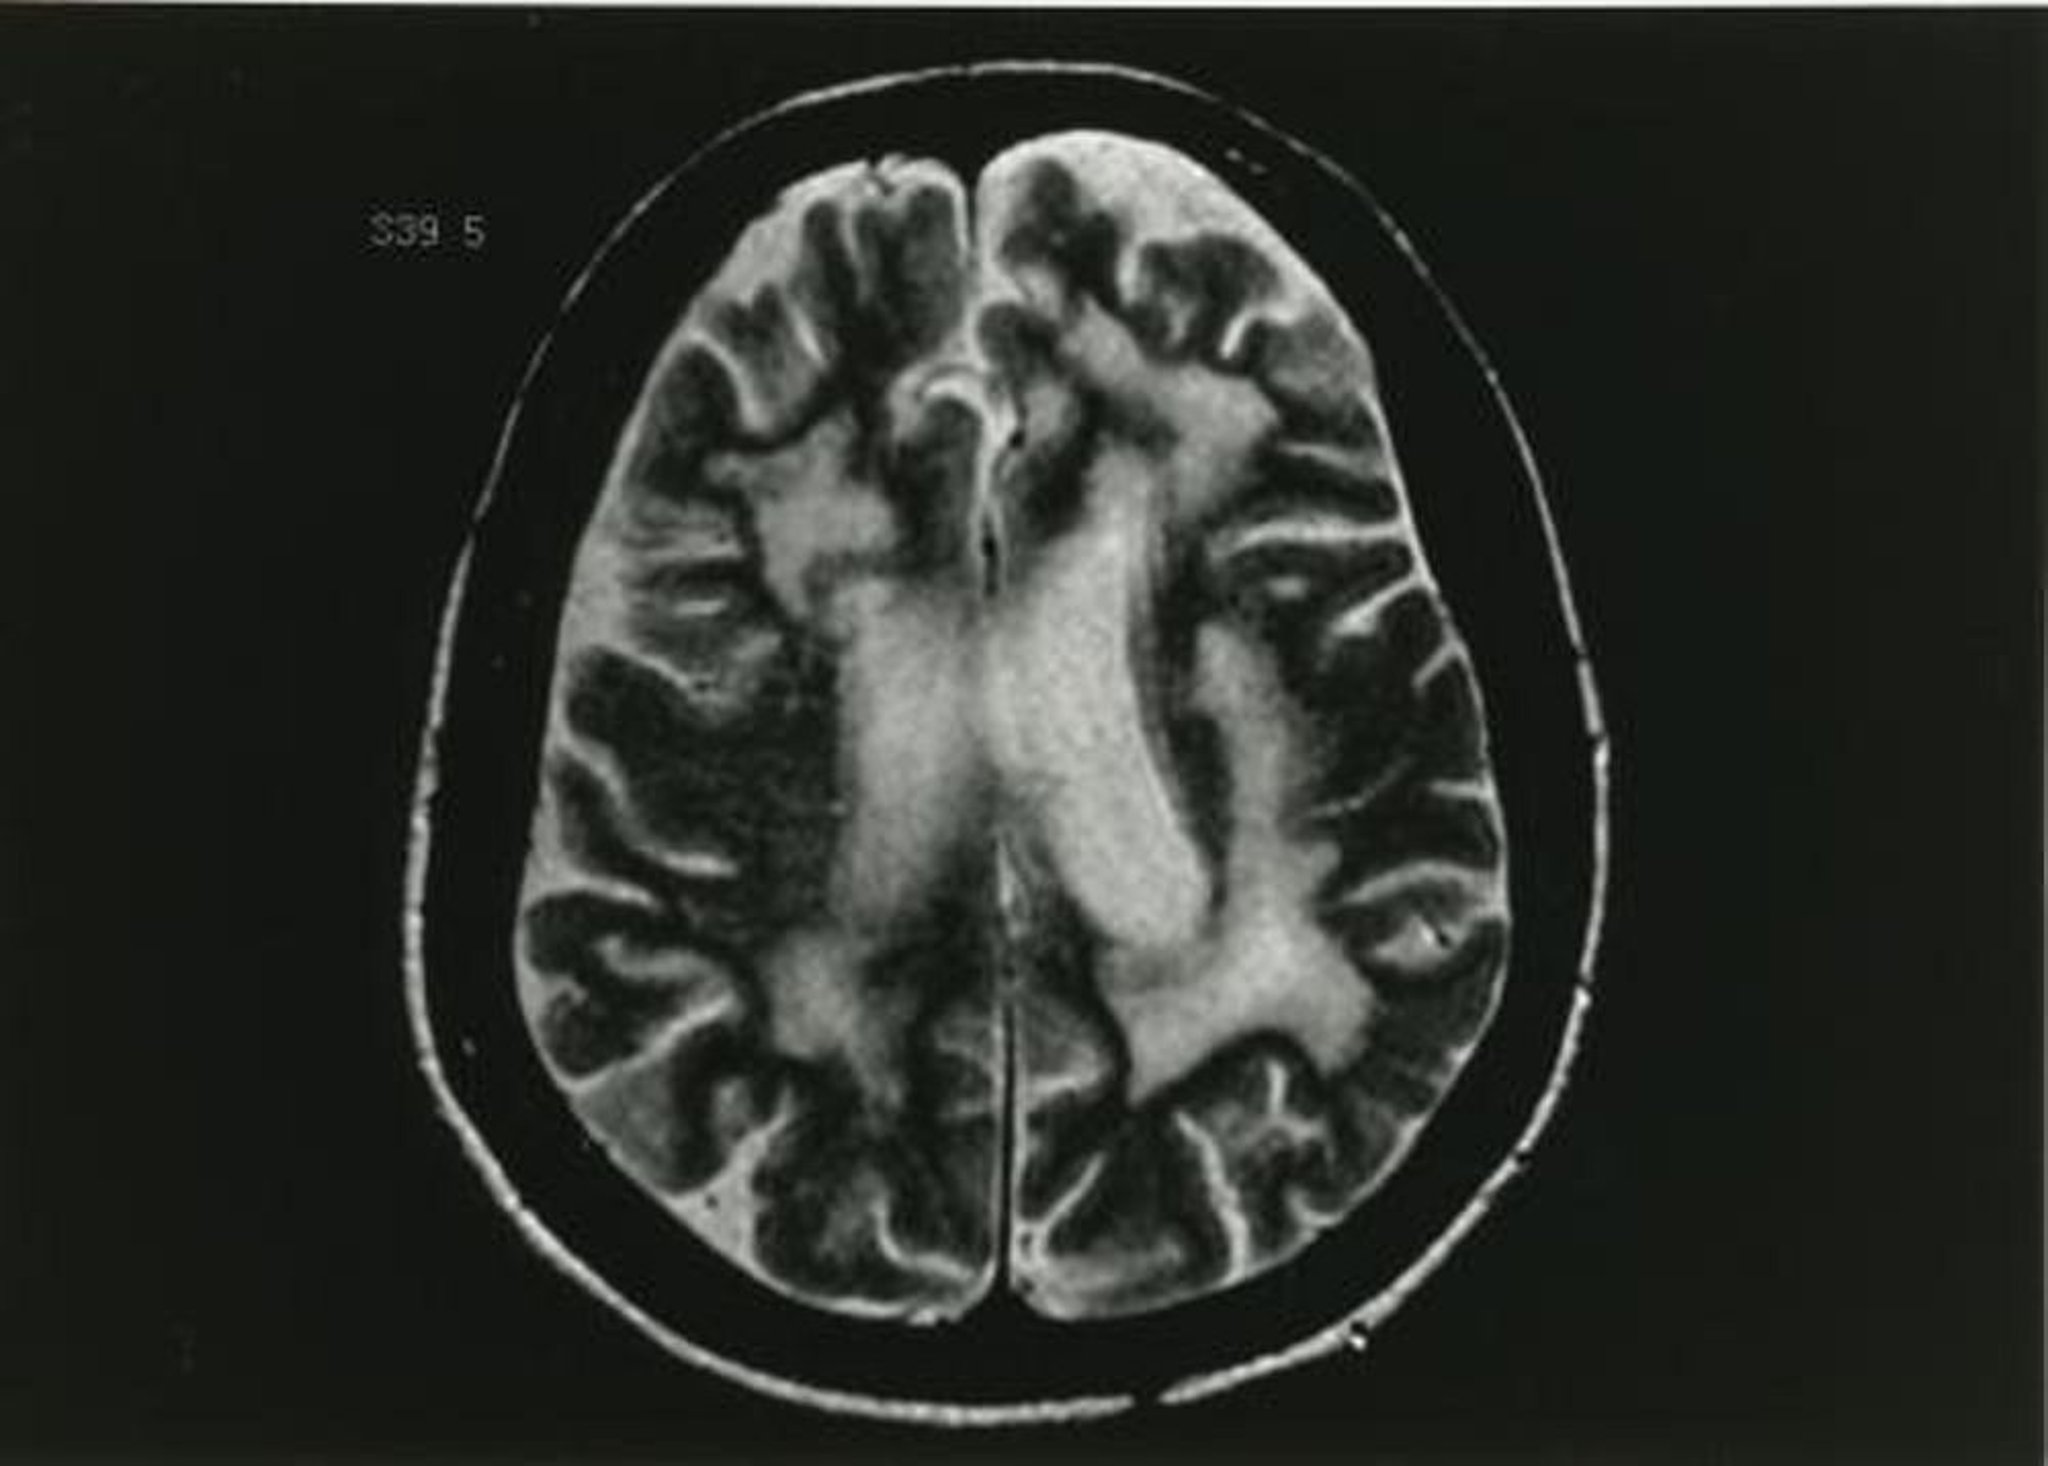

La diagnosi provvisoria di leucoencefalopatia multifocale progressiva si ottiene con la RM con mezzo di contrasto, che mostra una o più lesioni della sostanza bianca nelle immagini pesate in T2. Il mezzo di contrasto viene captato, in genere in maniera debole e periferica nel 5-15% delle lesioni. La TC può mostrare lesioni ipodense, non captanti, ma è significativamente meno sensibile della RM.

Questa immagine RM pesata in T2 mostra multipli cambiamenti nella sostanza bianca.

Immagine fornita da John E. Greenlee, MD.